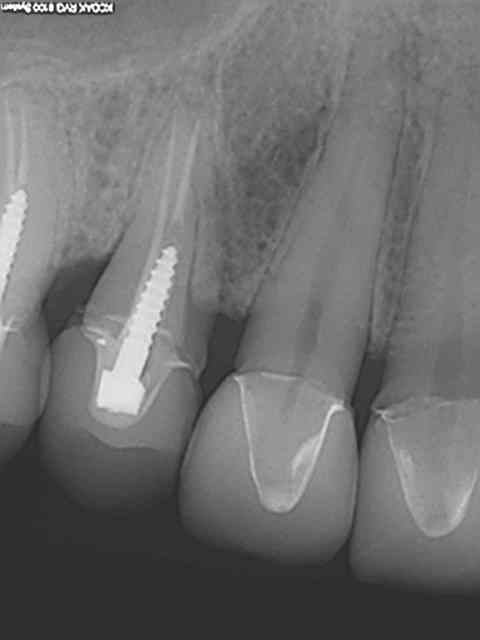

Bah des fois tu as la surprise de trouver des screw post composite sous des ceramo-metal et tu fais la taille direct puis tu cerequise!)

Eh oui, j'ai pas toujours été un bourrin, je me suis calmé pendant 2 ans..... le temps du cerec, mais il a bien fallu remettre les pieds sur terre ))))